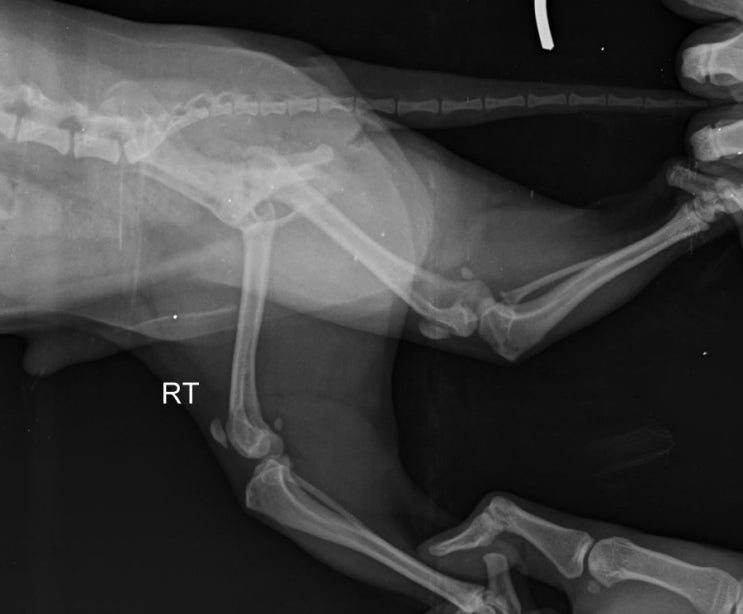

수술전 x-ray 평가입니다.

무릎도 많이 휘어져 있고, 슬개골 위치도 벗어난 상태입니다.